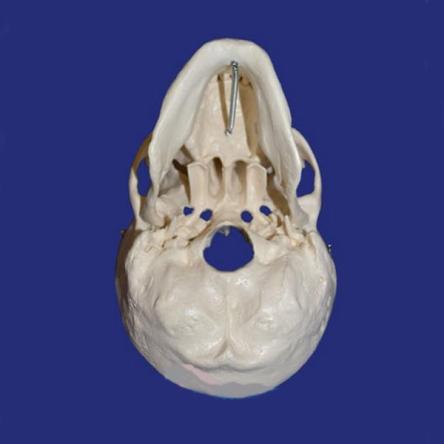

Детальная модель черепа человека A014 в натуральную величину с изображением всех детальных структур. Съемный свод черепа позволяет изучить внутреннее строение. Модель подходит для изучения в медицинских учебных учреждениях.

Эта модель классического черепа объединяет качество, удобство использования с низкой ценой. Наглядное пособие представляет собой высокоточную копию натурального человеческого черепа.

При необходимости, крышу можно снять для изучения внутренней поверхности. черепа. Всё это делает данный муляж лучшим выбором для студентов-медиков, для школ и самообразования, к тому же являясь оригинальным медицинским подарком.

Модель изготовлена из лёгкого и прочного ПВХ. В отличии от натуральных черепов, модель долговечна и не требует каких-либо специальных условий работы с ней и хранения.